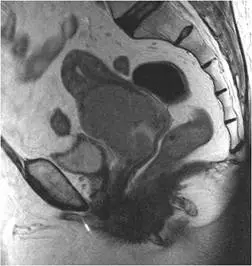

68 歲女性病患,已停經,主訴不正常陰道出⾎,磁振造影檢查如下圖。其最可能的診斷為何?

停經後不正常陰道出血合併磁振造影(MRI)見子宮頸部大型腫塊,最典型的診斷為子宮頸癌(cervical cancer)。本題考核考生對子宮頸癌 MRI 影像特徵的判讀,以及與其他婦科病灶(子宮肌瘤、子宮內膜癌、子宮內膜息肉)的鑑別診斷能力。

本題 MRI 影像為矢狀切面(sagittal view),影像顯示一個大型、不均質(heterogeneous)的軟組織腫塊,腫塊中心明顯位於**子宮頸(cervix)**區域。腫塊體積龐大,造成子宮頸明顯擴大變形,並可見腫塊向上侵犯子宮體下段(lower uterine segment)。

關鍵影像特徵:

- 腫塊以子宮頸為中心(cervix-centered mass),而非子宮腔(endometrial cavity)

- 腫塊呈中等至較高訊號強度,相對於正常子宮頸基質(cervical stroma)的低訊號,可見腫塊破壞正常子宮頸環形低訊號帶(disruption of the hypointense fibrous cervical stromal ring)

- 腫塊體積大,形態不規則,邊界不清

- 未見明顯宮腔內膜起源的特徵

此影像表現與子宮頸癌(cervical cancer)之 MRI 典型特徵高度吻合:T2 加權影像上呈現中高訊號的子宮頸中央腫塊,破壞